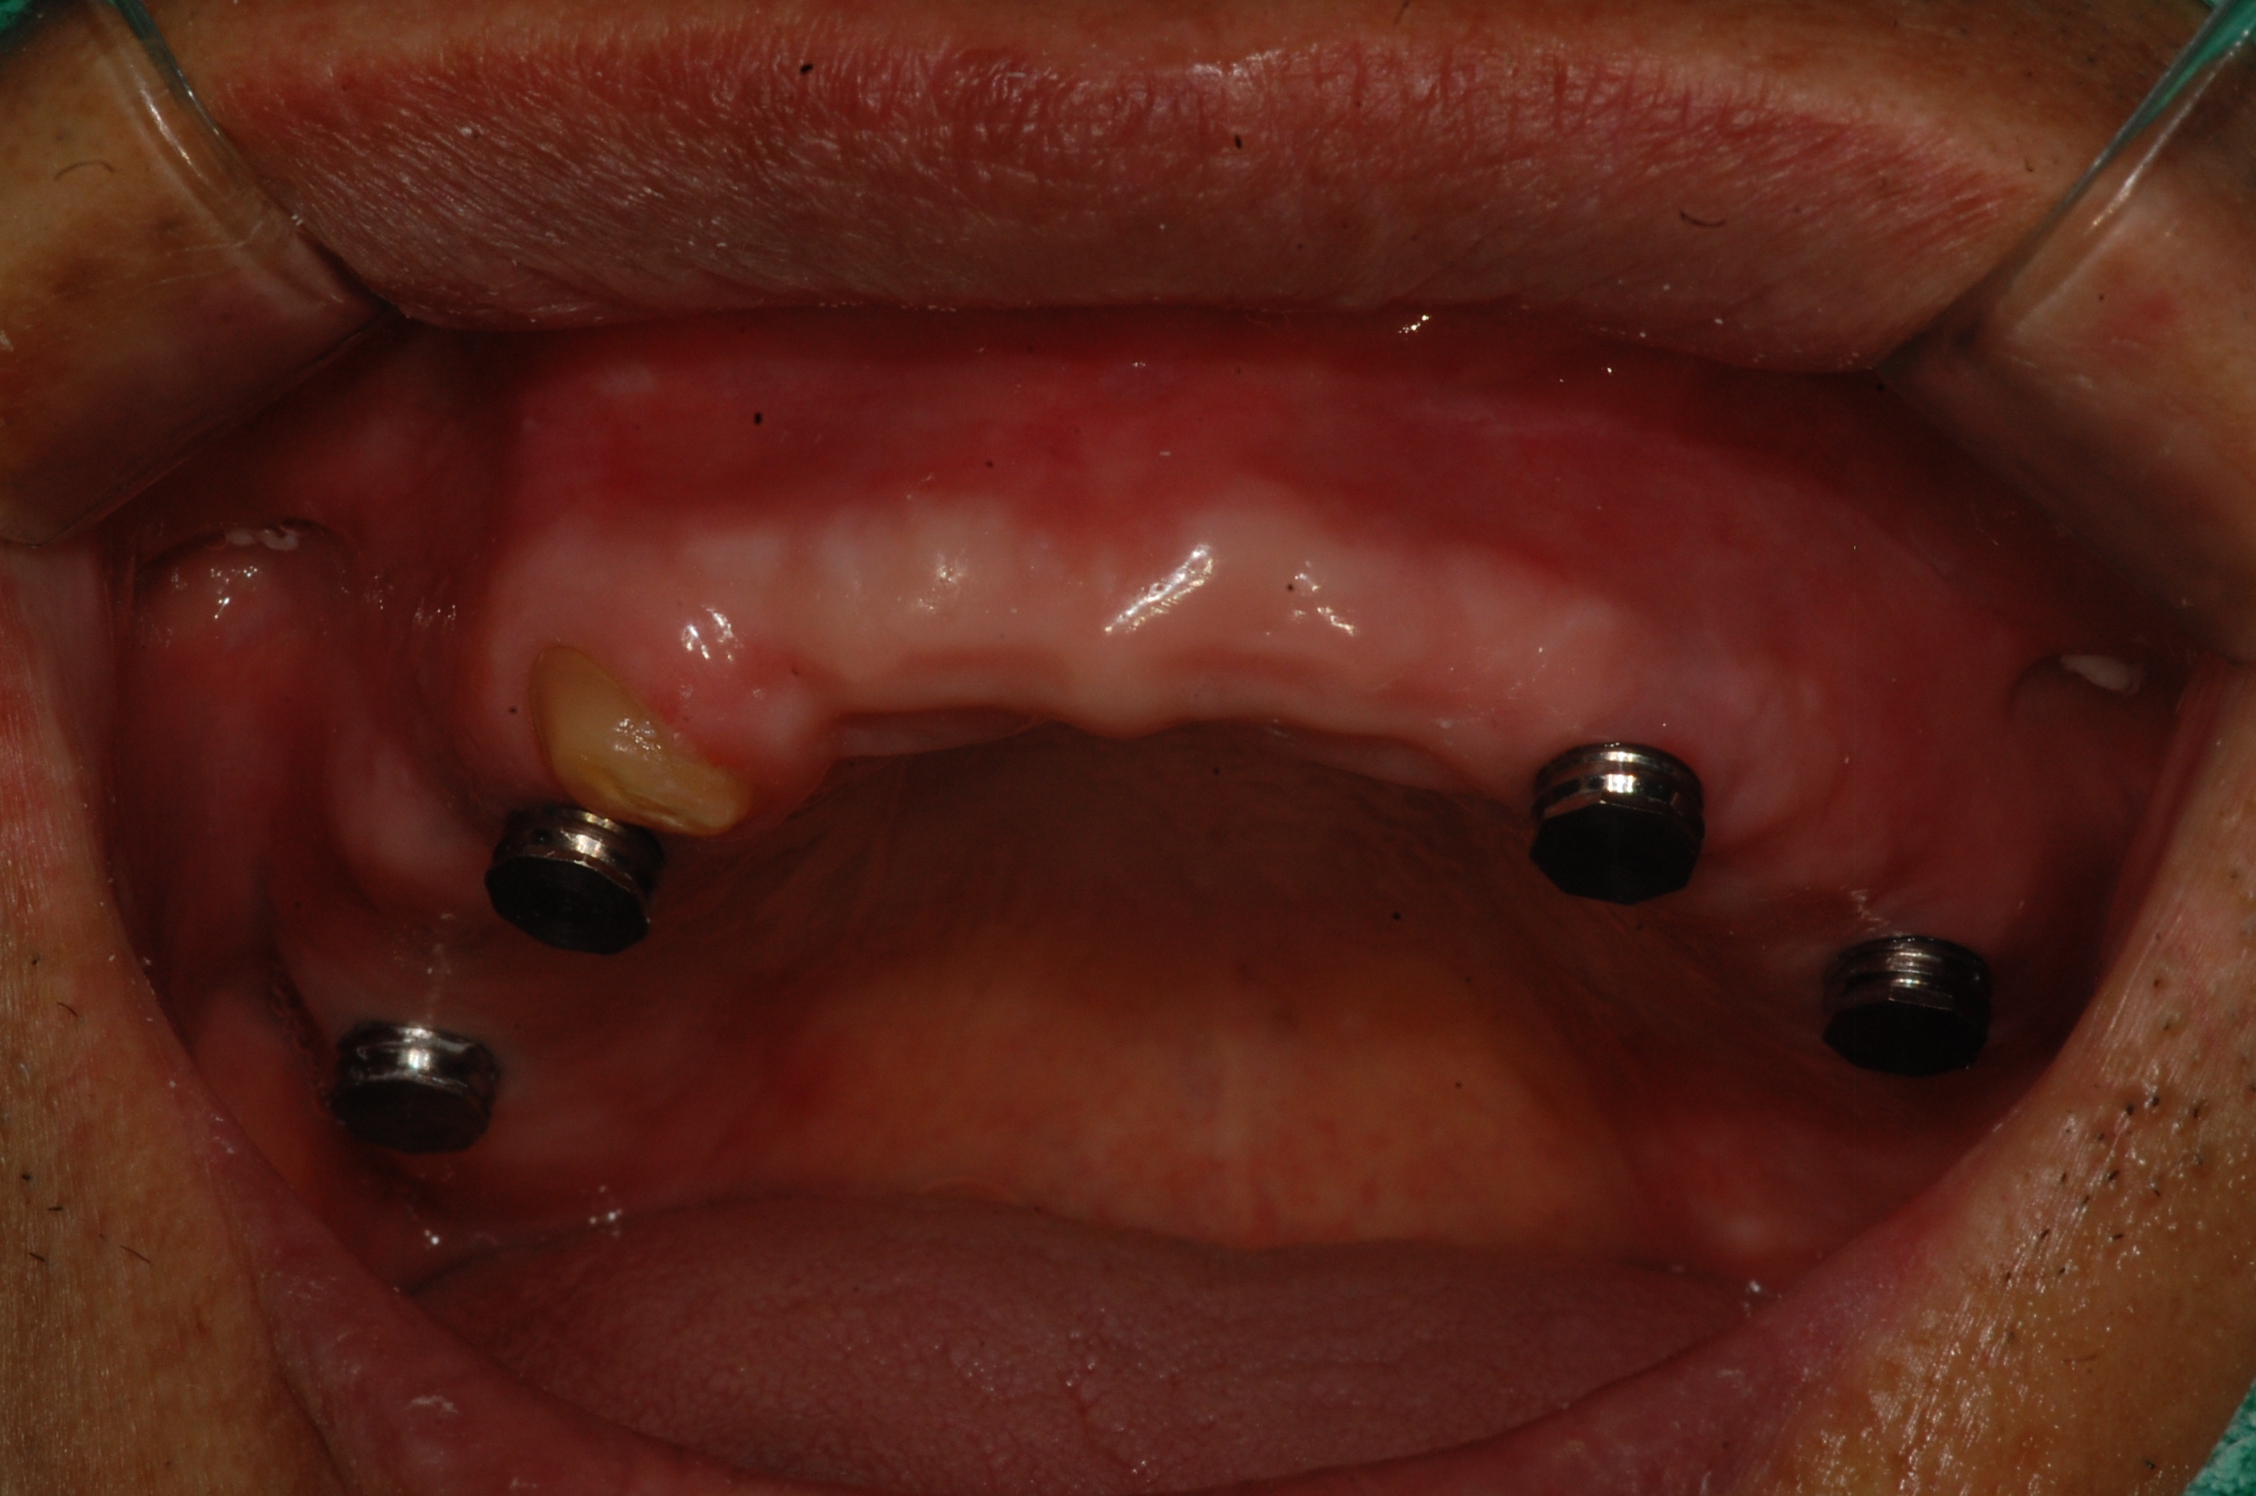

임플란트 지지틀니입니다.

임플란트에 똑딱이 같은 장치를 달아서 틀니를 쓰기 편하게 하는 방법입니다.